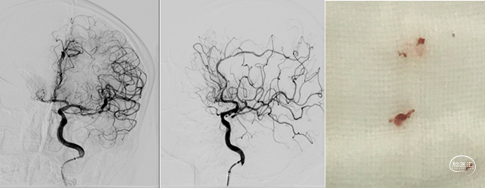

快速建立8F导引导管+CAT6中间导管建立路径,微导丝携微导管顺利通过左侧小脑后下动脉闭塞段。4/20取栓支架输送到位下图2;释放取栓支架下图3;取栓支架释放后造影血管未再通下图4。

等待5分钟后,部分回收微导管,钳夹血栓,上送中间导管,采用SWIM技术取栓,一次钳夹取出的暗红色血栓。复查造影见左侧小脑后下动脉完全再通。

术前术后对比

动态观察15分钟后,左侧小脑后下动脉血流通畅,右侧大脑后动脉远端血栓逐渐消融,持续静脉泵入替罗非班,逐级撤出各级导管,结束手术。

患者麻醉苏醒顺利,安返病房。术后查看患者意识清,言语清晰,四肢活动正常,头晕较前明显改善。继续给予内科药物治疗。次日复查CT未见出血转化,患者症状完全缓解。

结合患者病史,影像学及术中影像考虑患者栓塞可能性大,术后第3天完善TCD发泡试验可见心脏右向左大量分流,符合心源性反常栓塞特点,建议患者尽快完善经食道超声明确心脏情况,避免日后再发栓塞可能。